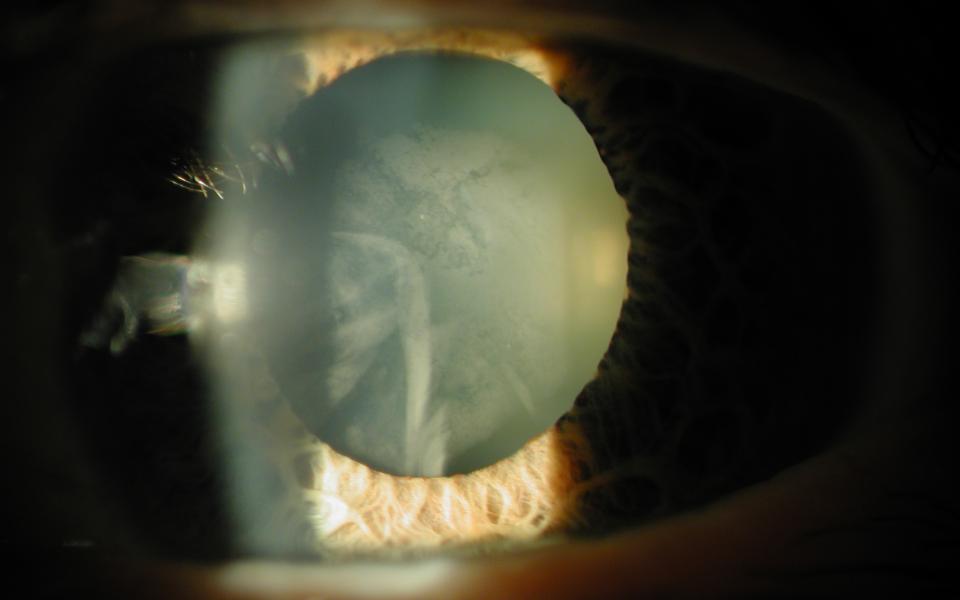

The Argentinan Flag sign more commonly occurs in patients with mature nuclear sclerosis. The anterior capsule is stained with trypan blue (Vison Blue). When the capsule is decompressed with a 25G